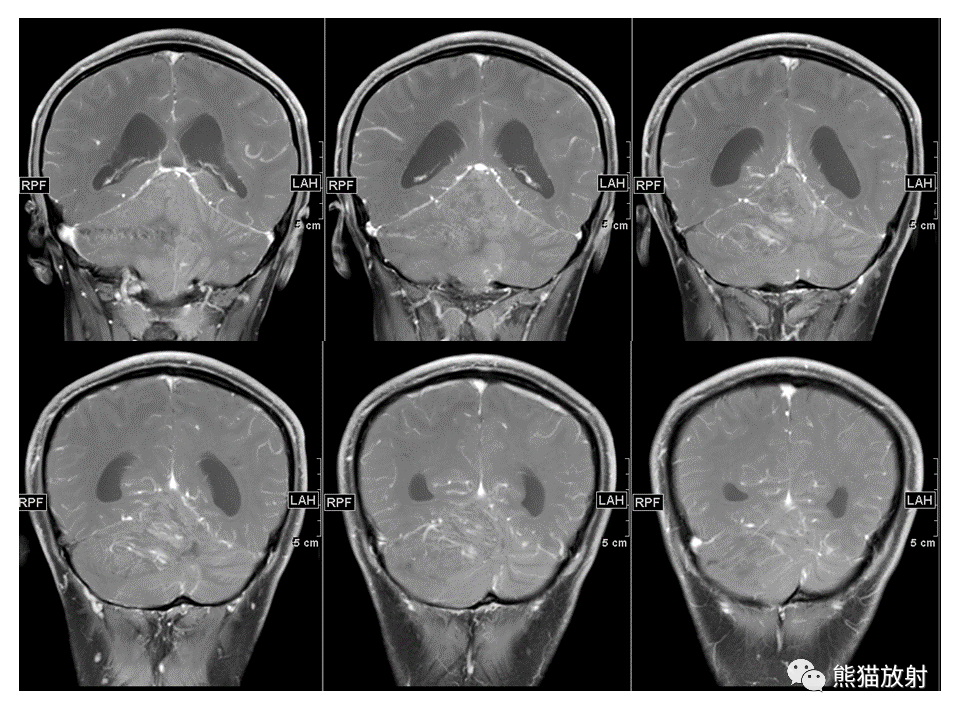

【PPT】小脑发育不良性神经节细胞瘤 VS 成人型髓母细胞瘤-3